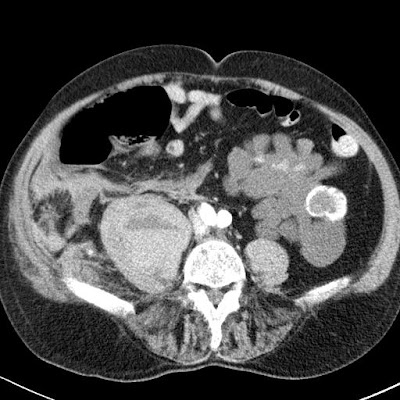

vénás fázis

Jobb oldalon a  m. psoas maior területén nagy bevérzés látszik, melyen belül egy folyadék-folyadék nívó határon artériás fázisban jelzett mennyiségű, vénás fázisban egyértelműen kivehető kontrasztanyag extravasatio látszik. Aktív vérzés.